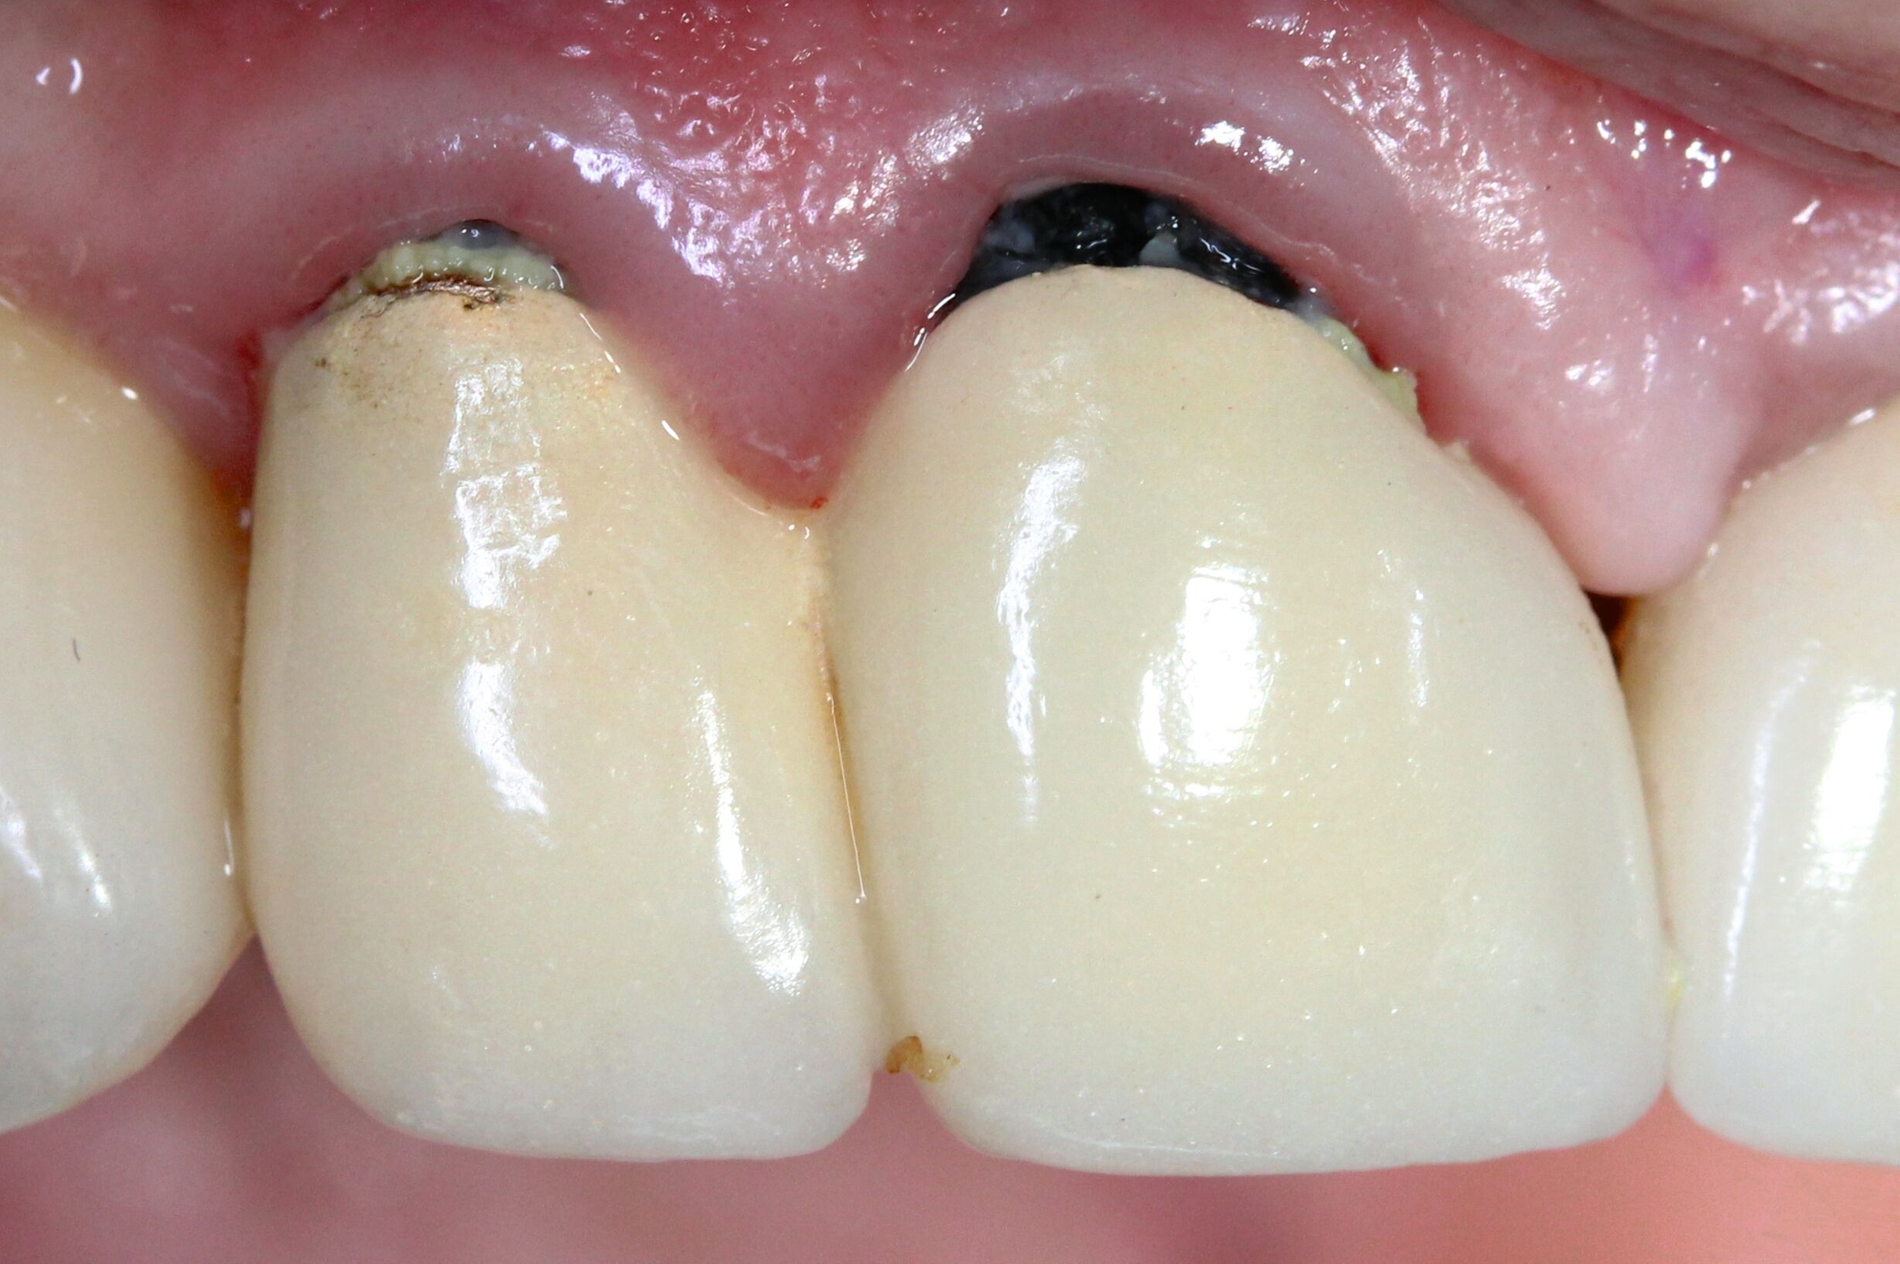

Silberdiamminfluorid ist eine wasserlösliche Verbindung, die aus Silberionen (Ag+), Ammoniak (NH₃) und Fluoridionen (F-) besteht. Ammoniak dient in dieser Verbindung als Stabilisator, indem es die Lösung alkalisch hält. Bei einer Konzentration von 38 Prozent entspricht das einer Konzentration von 44.800 ppm Fluorid und 255.000 ppm Silberionen. In seiner physikalischen Erscheinung ist SDF eine klare bis leicht gelbliche Flüssigkeit mit einem charakteristischen metallischen und leicht ammoniakartigen Geruch. Aufgrund der hohen Alkalität kann es bei Schleimhautkontakt zu leichten Reizungen kommen (Abbildung 2).

Eine bekannte Nebenwirkung bei Anwendung auf kariösen Läsionen ist die Schwarzfärbung des behandelten Bereichs (Abbildungen 3, 4). Verfärbungen können aber auch bei Applikation auf kariesfreien Wurzeloberflächen entstehen, diese sind jedoch mit einer professionellen Zahnreinigung gut zu entfernen (Abbildung 2).

Der Wirkungsmechanismus ist bislang nicht aufgeklärt. Die wesentlichen Verbindungen in SDF-behandelten Läsionen sind Silberphosphat, Silberoxid und Silbersulfid. Silberphosphat ist ein guter Photokatalysator [Yi et al., 2010], der spezifische chemische Reaktionen mit oder zwischen den verschiedenen beteiligten Verbindungen und Zahnstrukturen induzieren oder aber die auch ohne Licht eintretenden Reaktionen einfach beschleunigen könnte. Es wird vermutet, dass beispielsweise metallische Silbernanopartikel entstehen könnten [Li et al., 2019]. Abbildung 3 zeigt bräunliche Verfärbungen der Schleimhaut nach Lichteinwirkung.

Nebenwirkungen bestehen in lokalen Reizungen und temporären bräunlichen Verfärbungen der Gingiva und der Schleimhäute nach direktem Kontakt mit der SDF-Lösung, welche jedoch nach kurzer Zeit verschwinden. Personen mit Allergien gegenüber den Bestandteilen von SDF und gegenüber Silberverbindungen sollten kein SDF erhalten. Eine gravierende Nebenwirkung ist die dunkle Verfärbung der kariösen Läsion, was jedoch gleichzeitig der Indikator für die eingetretene Wirkung von SDF ist. Insgesamt kann die Behandlung jedoch als sicher eingestuft werden (siehe beispielsweise www.ada.org/resources/ada-library/oral-health-topics/silver-diamine-fluoride).